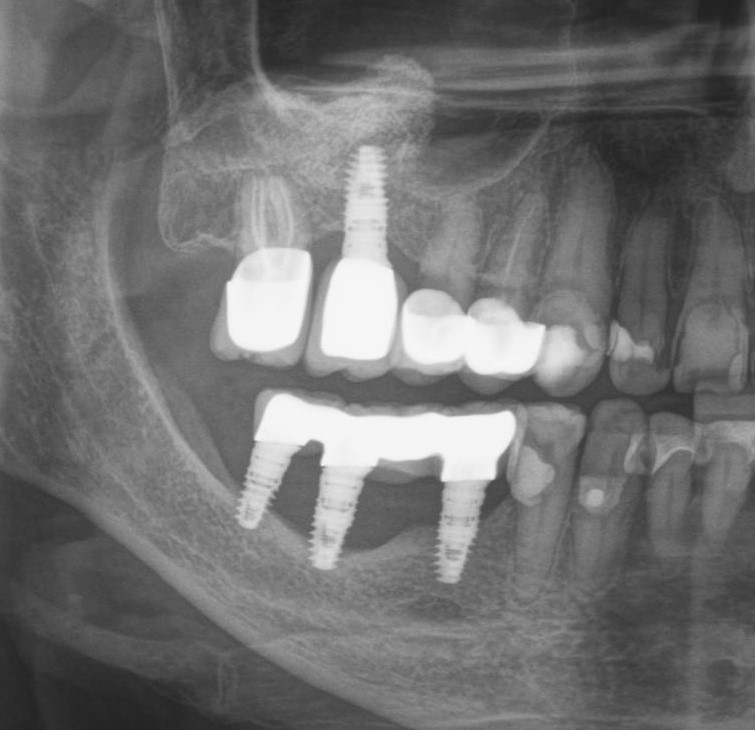

Дальше на очереди гуру планирования и расчетов.

Сразу ясно: что-то тут не так. Пациент был лишен 6-ого и 7-ого зуба на верхней челюсти справа. Но хирург почему-то установил имплантаты в проекции зубов 7 и 8. В связи с этим доктору-ортопеду и зубному технику пришлось извращаться и изготавливать вот такой ущербный мостовидный протез. Такая причудливая форма способствует забиванию и скоплению пищи под этим навесом. Именно это, собственно, и привело к критичной убыли костной ткани вокруг имплантатов.

Это чудо необходимо демонтировать и начинать сношаться с проблемой отсутствия зубов заново. Писать о том, что ценник в связи с этим подлетает до небес, думаю, не стоит. Не так ли? Ведь в переделку входят: